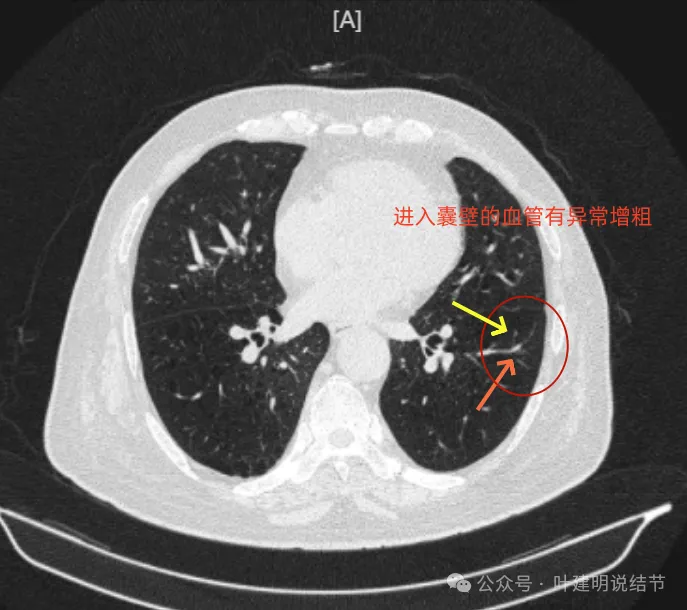

上图是病灶边缘部位有血管走向病灶侧,并达病灶的地方有异常增粗。